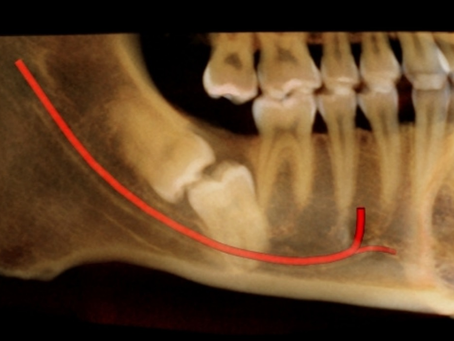

LASERTERAPIA PARA PARESTESIA

A parestesia consiste não ausência total ou parcial de sensibilidade em determinada região. Pode estar relacionada ao surgimento de...